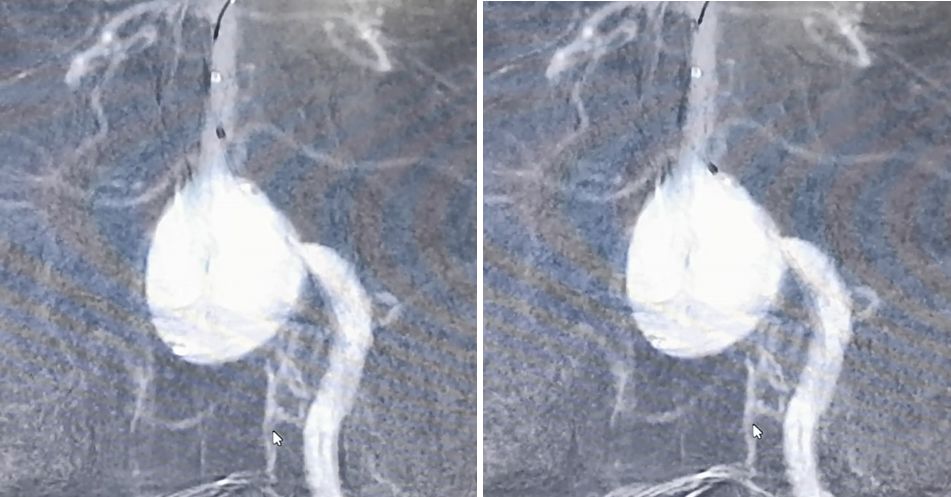

2019.5.25外院DSA

通过造影可以看到,动脉瘤主体位于右侧椎动脉,左侧椎动脉也有累及,不过左侧椎动脉PICA以远的部分纤细,考虑可以牺牲掉而不会影响基底动脉血供,但可以部分减少动脉瘤压力。左侧椎动脉为优势椎动脉,则应用PED装置保护并重建之。

经左椎动脉造影可见椎-基底动脉汇合部巨大动脉瘤,双侧椎动脉均有累及,以左侧椎动脉为主,右侧PICA与动脉瘤有一定距离,基底动脉稍受累及,AICA距离动脉瘤较近。